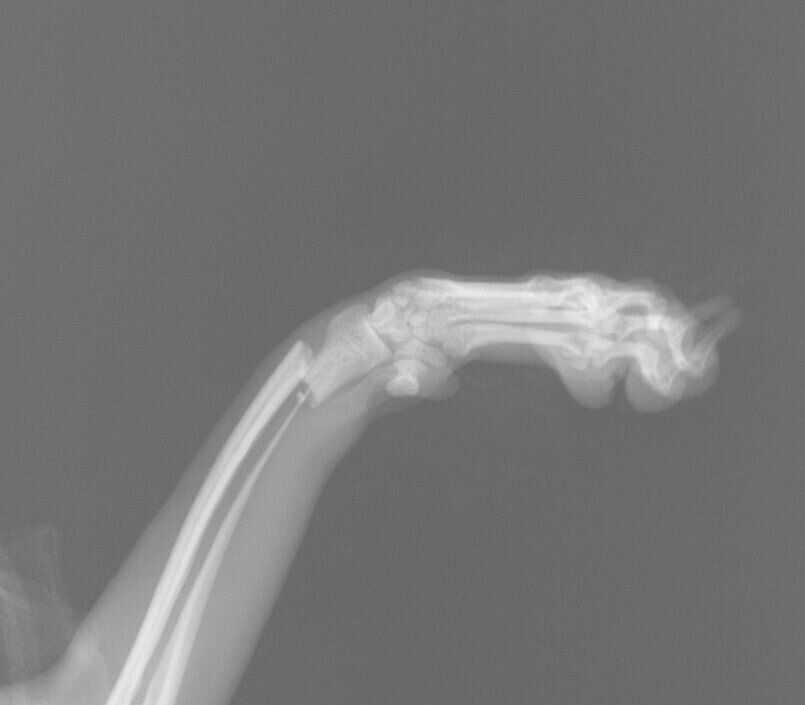

ソファから飛び降りただけでも折れる!? 若い犬でも注意すべき犬の骨折